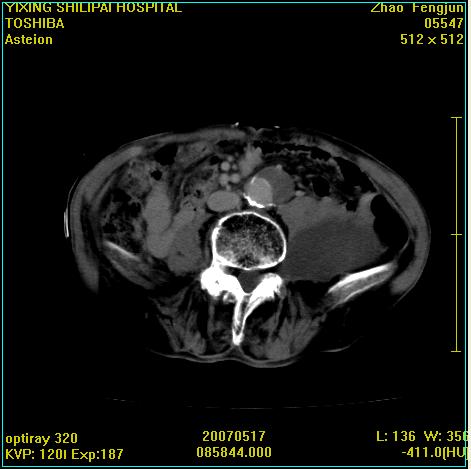

考虑:1、左侧腰大肌囊实性占位性病变(囊性神经根鞘瘤?);

2、右侧兰尾区囊性占位性病变(兰尾囊肿?囊腺癌?类癌?)

以下是引用xiaoniu在2007-5-26 10:45:00的发言:[br]腰大肌的病变应该没有问题,增强扫描还有轻度强化及细小血管影入内,应该排除脓肿,考虑占位性病变,腰大肌的占位多考虑:神经源性肿瘤。另外腹主动脉下端有真假腔的强化,考虑:主动脉夹层。[br][br][本贴已被 xiaoniu 于 2007-5-26 10:46:39 修改过]

以下是引用老爱克斯新网客在2007-5-26 18:26:00的发言:[br]1左下腹囊实性占位肿块,增强后不均匀强化,位于脊柱旁,椎体骨质无破坏软组织无肿胀,考虑神经源肿瘤神经鞘瘤可能大,2右下腹囊性占位性病变,增强后囊壁强化,考虑阑尾囊肿或囊腺瘤,